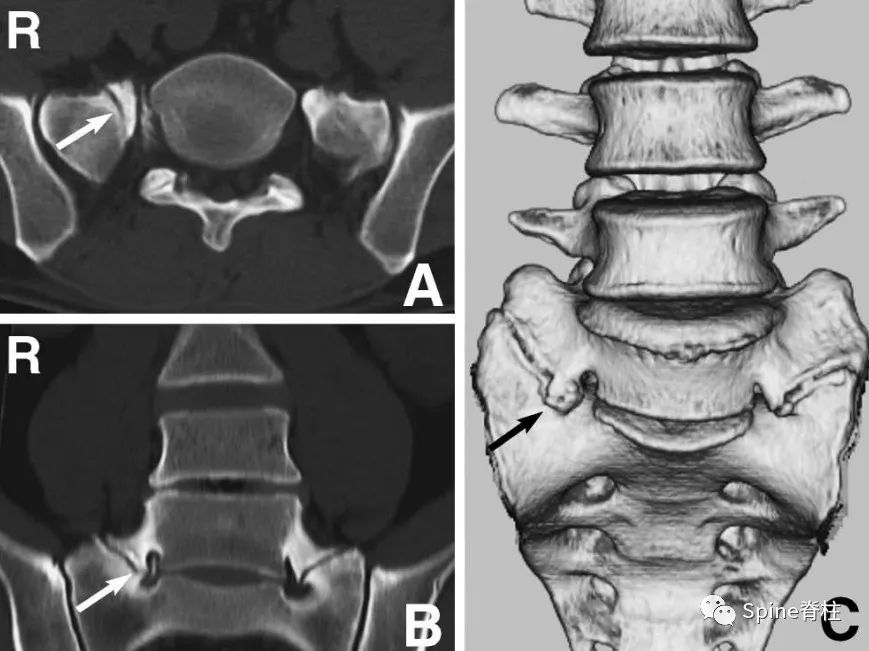

图示:确诊为 LSTV IIb型(具体分型详见: 你注意过腰5椎体的横突吗? ),患者L5神经根右下肢放射痛通过选择性根管造影确诊,增生肥大的横突与骶骨形成的假关节压迫椎间孔外侧远距离处的L5神经。